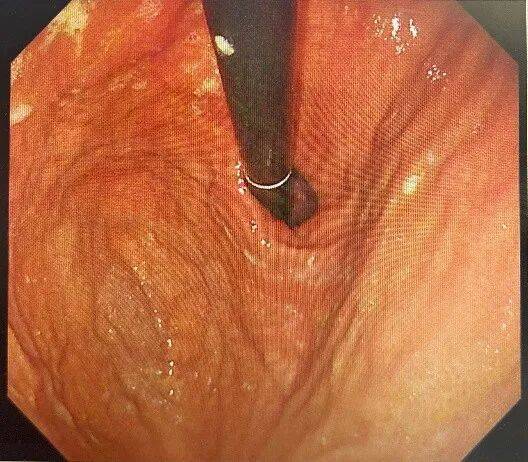

明确诊断后予抑酸、溶石、补液等对症处理,2周复查胃镜提示:胃多发溃疡(H1期)。胃底、胃体黏膜光光滑,胃石已溶解消除。